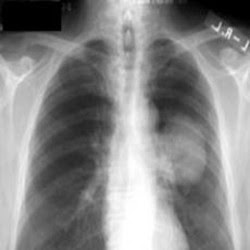

Kronik bronşitte solunum yollarındaki kalıcı ve ilerleyici değişiklikler öksürük ve balgama neden olur. Kronik bronşitin ilk belirtisi 2 ardışık yılda, yılın en az 3 ayı boyunca süren öksürük ve balgamdır.

Amfizem akciğerlerde bulunan hava keseciklerinin (alveoller) genişlemesi ve harap olmasıdır. Yapılan araştırmalara göre, amfizem ve kronik bronşit olgularının % 90’ının nedeni sigara kullanımıdır.

KOAH yavaş seyir gösterir ve zaman içinde kötüleşir. Hastalığın ilerleme hızı ve belirtilerin şiddeti kişiden kişiye farklılık gösterir. Başlangıçta sadece egzersiz benzeri bedensel faaliyetler sırasında nefes darlığı olurken hastalık ilerledikçe yürüme, giyinme gibi günlük faaliyetler sırasında nefes darlığı gelişebilir.